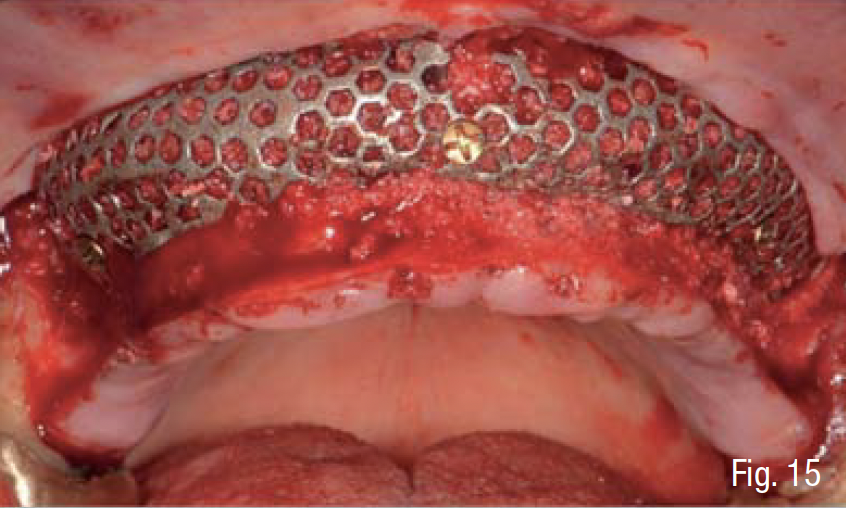

La corticale esterna del sito ricevente è stata perforata (Fig. 11) al fine di promuovere la migrazione delle cellule osteogeniche e osteoprogenitrici e la rivascolarizzazione dell’innesto osseo al di sotto della griglia. L’osso autologo del paziente è stato mescolato in rapporto 1:1 ad osso eterologo di origine bovina ad alta porosità (Zcore®, Osteogenics Biomedical, Lubbock, Texas), tutto idratato con sangue venoso periferico del paziente (Fig. 12). La griglia customizzata è stata quindi riempita con il materiale da innesto, posizionata a livello della superficie vestibolare del mascellare, e fissata con 5 mini-viti di sintesi in titanio di lunghezza 6-9 mm (BTK screw, Biotec Srl, Dueville, Vicenza, Italy), verificandone la perfetta stabilità e la conseguente assenza di micro- o macro- movimenti. Al fine di rispettare il principio di “esclusione cellulare” della GBR, al di sopra della griglia è stata applicata una membrana in collagene cross-linkato (Cytoplast RTM, Osteogenics Biomedical, Lubbock, Texas), fissata tramite chiodini di titanio sul lato vestibolare e suturata alla mucosa sul lato palatale (Figg. 13-17).

Infine, è stata eseguita un’attenta chiusura di prima intenzione dei lembi chirurgici, mediante una sutura a doppio strato, costituita da una linea di punti a materassaio orizzontale e da una linea di punti staccati singoli, per garantire una chiusura ermetica della ferita (SERAFAST 5/0, Serag-Wiessner, Naila, Germany) (Figg. 18, 19). Nei 7 giorni consecutivi il paziente ha proseguito la terapia antibiotica a base di amoxicillina e acido clavulanico e una terapia antiinfiammatoria a base di nimesulide; risciacqui con clorexidina 0.20% 3 volte al giorno per 2 settimane; e non ha utilizzato la protesi parziale rimovibile sempre per 2 settimane. Dopo 9 mesi, essendo stata confermata una sufficiente mineralizzazione del volume osseo al di sotto della griglia mediante una CBCT post-operatoria (Figg. 20-22), è stata pianificata una chirurgia computer-guidata per inserire gli impianti in modo protesicamente guidato (Figg. 23, 24).